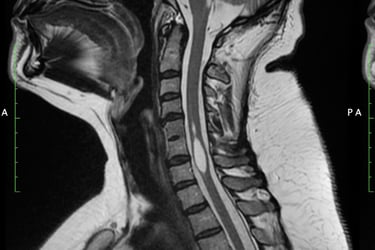

Is a neurological disorder in which a fluid-filled cyst (syrinx) forms within the spinal cord. The syrinx can get big enough to damage the spinal cord and compress and injure the nerve fibers that carry information to and from the brain to the body. Some studies have found the prevalence of syringomyelia to be 8.4 cases in 100,000 in the U.S.

In syringomyelia, the watery liquid known as cerebrospinal fluid (CSF)—which surrounds and protects the brain and spinal cord—builds up within the tissue of the spinal cord, expands the central canal, and then forms a syrinx. Generally, a syrinx develops when the normal flow of CSF around the spinal cord or lower brain stem is disturbed. When syrinxes affect the brain stem, the condition is called syringobulbia.

MRI Image of the cyst